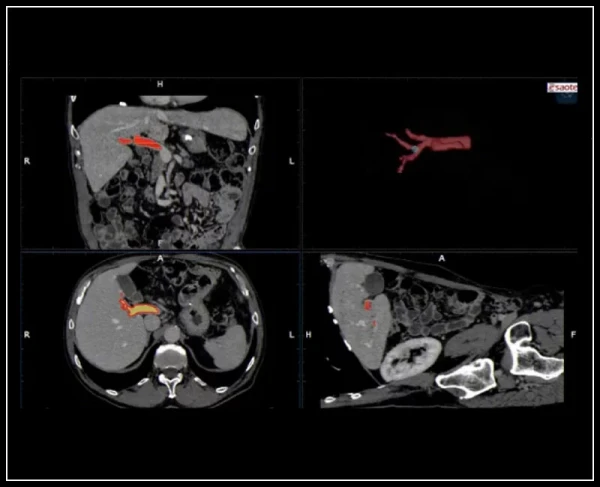

Virtual Navigator termoyadroviy texnologiyasining yangi darajasi: bir tugmani bosish orqali tomir segmentatsiyasi tasvirlarini avtomatik ro'yxatga olish va aniq korrelyatsiya qilish, nafas olish paytida harakatning avtomatik kompensatsiyasi

Muntazam BodyMap va Virtual Biopsiya tekshiruvlari uchun virtual navigatsiya